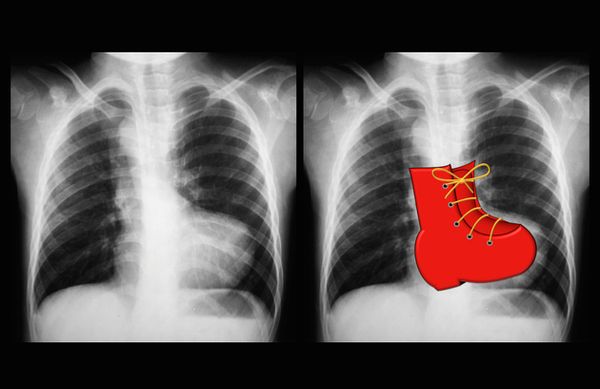

3. Рентгенография органов грудной клетки. Проводится для оценки:

- Состояния лёгких — для тетрады Фалло характерна повышенная прозрачность лёгочных полей из-за снижения кровотока в лёгких, уменьшение корней лёгких.

- Конфигурации сердца — при этом пороке верхушка сердца приподнята и закруглена, талия сердца углублена и сглажена за счёт западения лёгочной артерии, наблюдается форма сердца по типу «деревянный башмачок».

- Размеров полостей сердца — при тетраде Фалло в косой проекции увеличенный правый желудочек оттесняет кзади и приподнимает невыраженный левый желудочек.

Форма сердца по типу «деревянный башмачок» [11]

В боковой проекции рентгенография позволяет обнаружить смещение аорты.